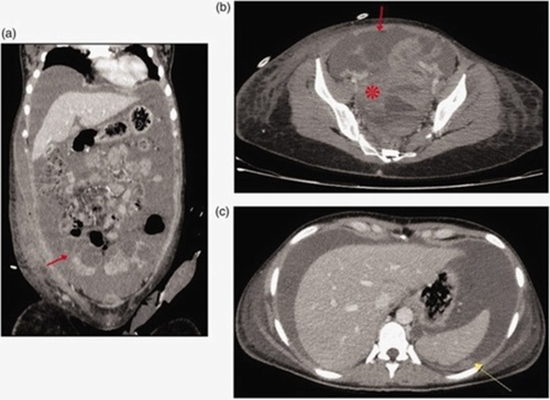

Spontaneous ovarian hyperstimulation syndrome is an extremely rare condition, especially in nonpregnant women who do not exhibit exogenous ovarian stimulation. Herein, we present a case of spontaneous ovarian hyperstimulation syndrome in a 28-year-old nonpregnant woman who presented with life-threatening multiorgan dysfunction. Initial imaging studies and tumor marker assessment suggested the presence of a malignant ovarian tumor, posing substantial diagnostic challenges. The patient underwent emergency surgery due to severe hemorrhagic shock. Intraoperative findings revealed irregular and deformed ovaries; however, histologic examination showed luteinizing hemorrhagic cysts, leading to a diagnosis of spontaneous ovarian hyperstimulation syndrome. This case highlights the importance of considering spontaneous ovarian hyperstimulation syndrome in the differential diagnosis of ovarian enlargement with ascites, even in the absence of pregnancy or ovarian stimulation. It also underscores the critical role of expert radiological interpretation in such complex cases.